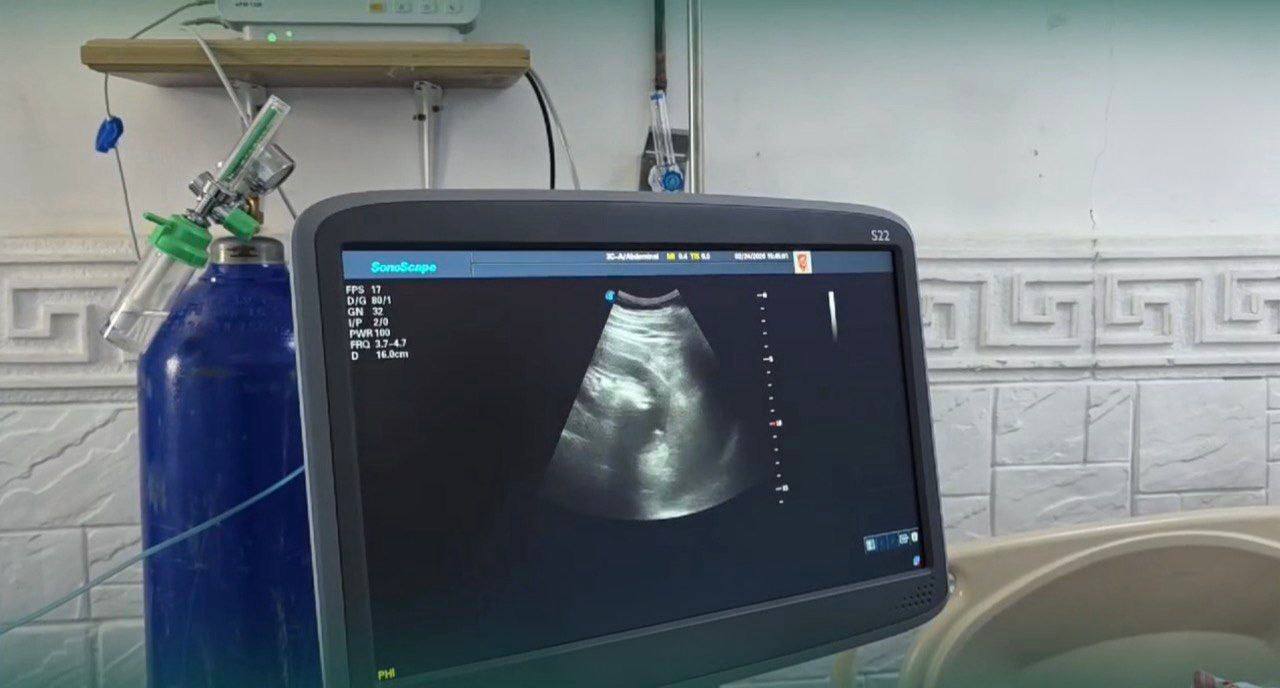

قدّمت منظمة “ميدغلوبال” جهاز (إيكو) متطوراً إلى مشفى دير الزور الوطني، وذلك لدعم القطاع الصحي وتعزيز قدراته التشخيصية والعلاجية. ويضم الجهاز مسبارين رئيسيين، مسبار قلبي مخصص لتصوير القلب وتحبيل بنيته ووظائفه بدقة عالية، ومسبار عميق يتيح إجراء تصوير متقدم للأعضاء الداخلية في الجسم، ما يساهم في تحسين جودة التشخيص وسرعة التدخل الطبي.